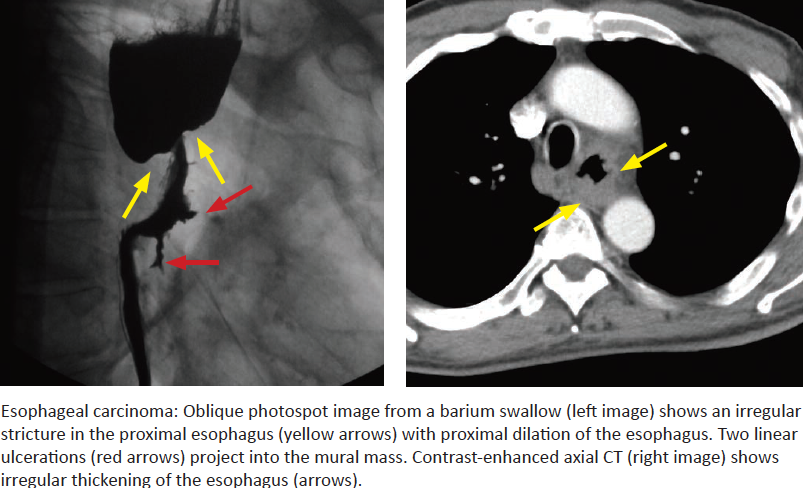

Esophageal Carcinoma

Imaging appearence? How to differentiate the uncommon “varicoid” appearing esophageal CA with a varices?

What are the twp kinds of esophageal CA? Where in the esophagus do each of these occur usually? Risk factors?